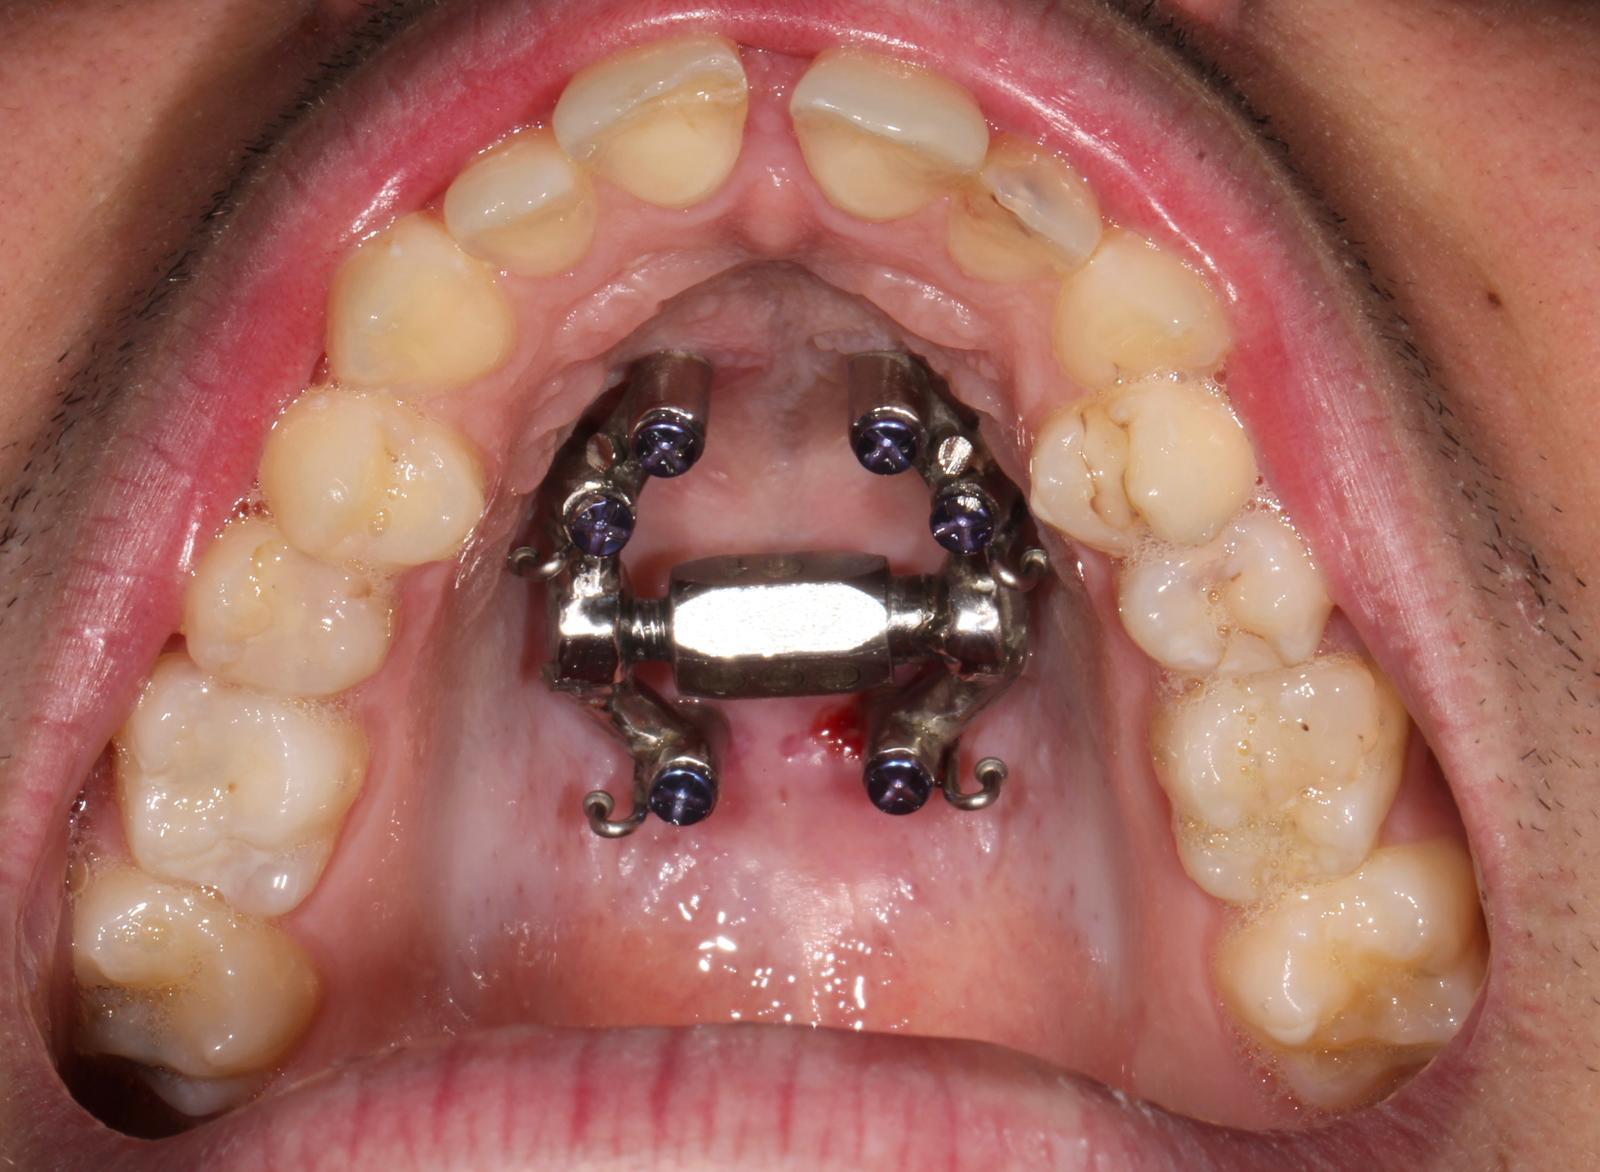

La técnica DS Xpander no es un tratamiento convencional; su enfoque técnico-clínico avanzado garantiza un procedimiento totalmente personalizado, maximizando la eficacia y la predictibilidad de los resultados finales. A diferencia de los aparatos de expansión tradicionales, que a menudo ejercen una presión excesiva sobre los dientes, este sistema utiliza microtornillos de anclaje esquelético. Estos dispositivos aplican la fuerza directamente sobre el hueso maxilar, evitando inclinaciones dentales indeseadas y garantizando que la expansión sea puramente ósea y no solo dental.

Al actuar directamente sobre la base ósea, logramos ensanchar el paladar de forma armónica y estable. Este proceso es fundamental para ganar espacio en casos de apiñamiento severo o para corregir mordidas cruzadas que, de otro modo, requerirían cirugías ortognáticas mucho más complejas. En nuestra clínica, la aplicación de la técnica DS Xpander representa un salto cualitativo en la ortodoncia avanzada, ofreciendo alternativas reales a pacientes que buscan una sonrisa funcional sin intervenciones hospitalarias invasivas.